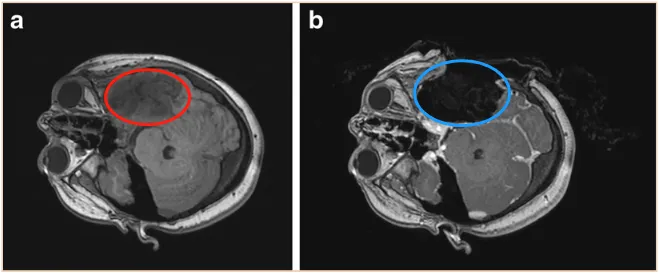

为了给孩子争取全切的机会,小乐一家转诊至德国INI,寻求Di Rocco教授的帮助。幸运的是,第二次手术十分顺利,全程使用术中神经电生理学监测,并在配备术中磁共振成像(iMRI)的手术室中通过导航引导方法实现了肿瘤全切。术后3年,小乐始终接受密切的随访,未见复发。

案例来源:Neurosurgical tools to extend tumor resection in pediatric hemispheric low-grade gliomas:iMRI